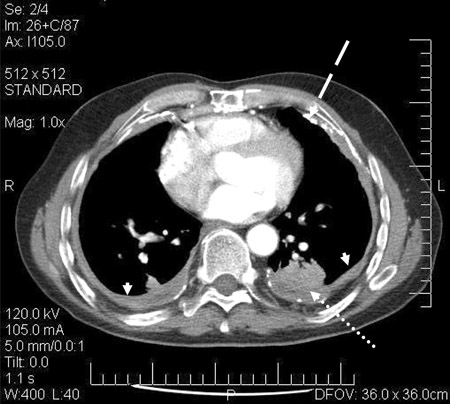

CT scan confirming symmetrical thickening (arrowheads) with a calcified pleural plaque (broken arrow, top right) and an area of rounded atelectasis (Blesovsky sign; dotted arrow, bottom right)

Adapted from BMJ Case Reports 2009; doi:10.1136/bcr.06.2008.0253